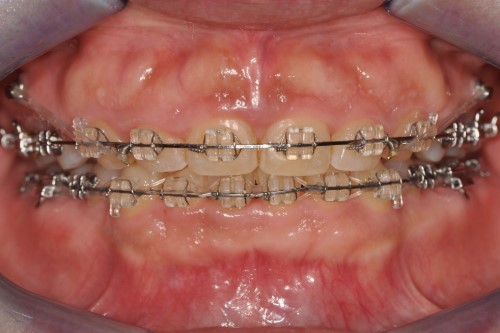

구강 내를 확인해 보니 양쪽 소구치 4개가 없는 상태였습니다.

예전에 다른 곳에서 발치교정을 계획하며 소구치 발치는 이미 진행했지만, 여러 사정으로 인해 교정치료를 시작하지 못한 채 시간이 지난 케이스였습니다.

위쪽은 발치한 공간이 그대로 남아 있었고, 아래쪽은 송곳니가 뒤로 쓰러지면서 발치 공간이 거의 사라진 상태였습니다.

앞니는 매우 깊게 물려 있어, 입을 벌리고 봐도 아래 앞니가 거의 보이지 않을 정도였습니다.

이 목표를 달성하기 위해, 교정용 미니스크류를 적절한 위치에 식립해 치아를 견인하는 방향과 힘의 크기를 정밀하게 조절하였습니다.

치료가 진행되면서 윗니에 가려 보이지 않던 아래 앞니도 점차 모습을 드러내기 시작했습니다.